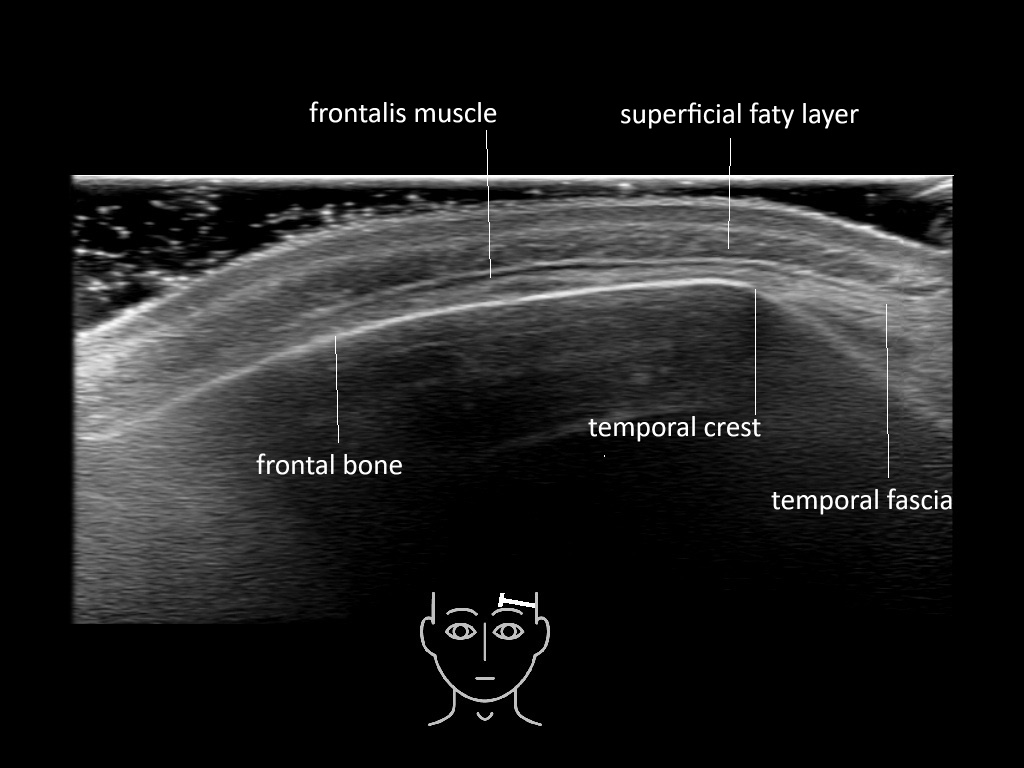

In this section you will learn more about the different layers of the face with the use of ultrasound. When you click on the secondary ultrasound image, you will see the different structures as an overlay. This will help to train yourself to recognize the different layers of the face.

Study the first image to recognize the different layers. If you are sure about the layers, swipe to the second image to view the answer (if applicable).